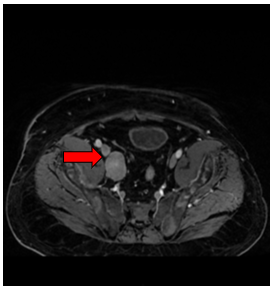

- Chụp cộng hưởng từ tiểu khung: (14/03/2025)

+ Hình ảnh u tuyến tiền liệt kích thước 30x40mm, xâm lấn túi tinh phải.

+ Các ổ tổn thương xương cùng, xương chậu, cổ xương đùi 2 bên, hạch cạnh bó mạch chậu bên phải kích thước 31x22mm - Theo dõi thứ phát

Hình 1. Hình ảnh chụp cộng hưởng từ tiểu khung: Hình ảnh u tuyến tiền liệt kích thước 30x40mm, xâm lấn túi tinh phải (mũi tên màu đỏ)